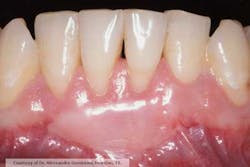

Fig. 1: Initial situation, before free gingival graft. Note the lack of gingiva buccal to teeth Nos. 24 and 25.

Fig. 2: Follow-up at eight weeks. The free gingival graft was successful in increasing the amount of gingival adjacent to teeth Nos. 24 and 25.